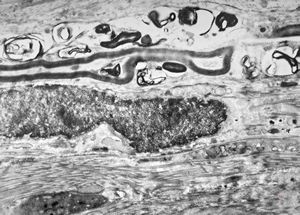

F,13y. | n.suralis … axonal neuropathy … Charcot-Marie-Tooth disease

Demyelinized nerve with bands of Büngner (square, inset) . P- perineurium, | E - epineurium. (Human, sural nerve.) Scale 0.2 mm.